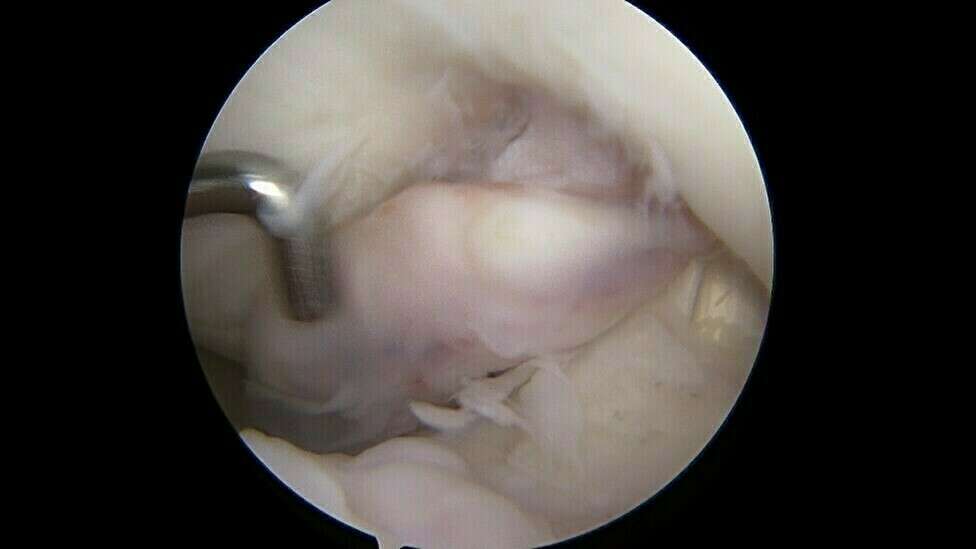

En l’absence d’évolution spontanément favorable, le traitement est systématiquement chirurgical et consiste à retirer ce nodule d’arthro-fibrose sous arthroscopie au cours d’une hospitalisation de courte durée en Chirurgie Ambulatoire. Lors de l’intervention chirurgicale, le chirurgien s’assurera de la récupération de l’extension complète du genou.

Galerie photo